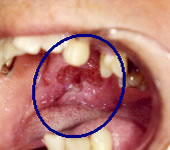

やや進行した咽頭癌

放射線、抗癌剤治療後

右中咽頭に癌があります。

放射線、抗癌剤治療により改善しました。

個人情報保護のため、他施設の例を一部改変して提示しております。